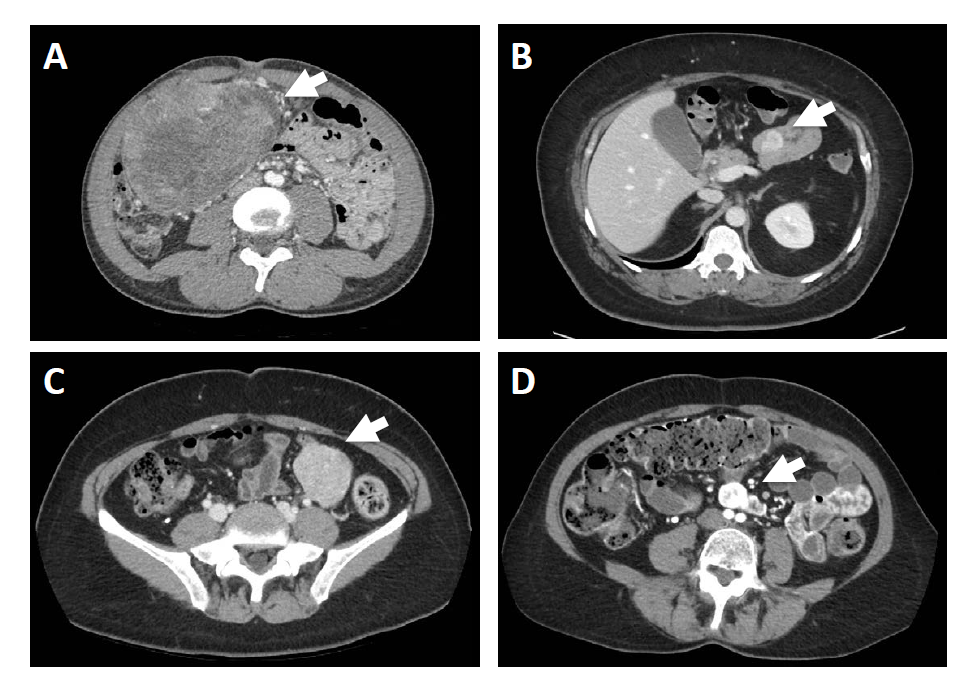

Gastrointestinal Stromal Tumors of the Small Intestine

- GIST is a genetically heterogeneous disease caused by mutations in KIT (70 to 80%), PDGFR, the RAS pathway (K-ras, H-ras, N-ras, BRAF, NF1), SDH A to Dsubunits, FGFR1, and ETV6-NTRK3, among others.

- Cytoreductive surgery in selected patients with metastatic GIST has comparable outcomes to second-line systemic therapy.